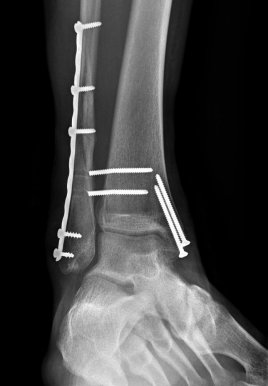

On Dec 30, 2011, I fell on the ice and broke my fibula and tibia and had to have surgery.

I had never broken my ankle. I had never had surgery before or anesthesia. Yikes!